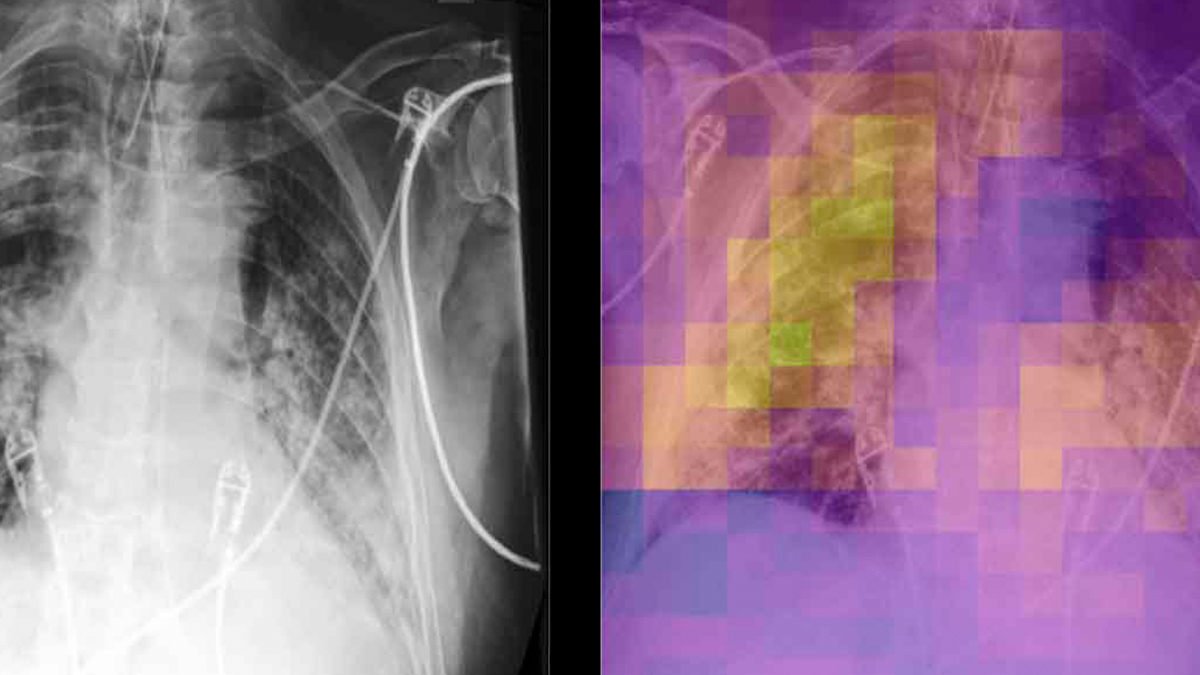

Medical Imaging Augmented With Ai Nvidia